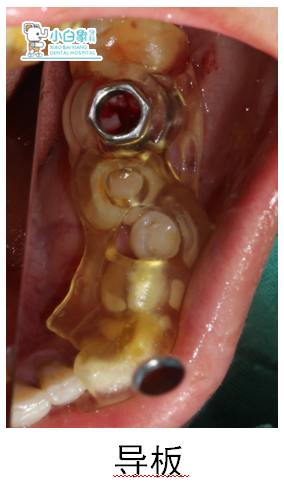

2017年5月28日,36必兰局麻下拔除,清理牙槽窝,在种植导板指导下备洞,植入百康5.0*8mm种植体一枚,植入Bio-oss骨粉,覆盖骨膜,严密缝合。